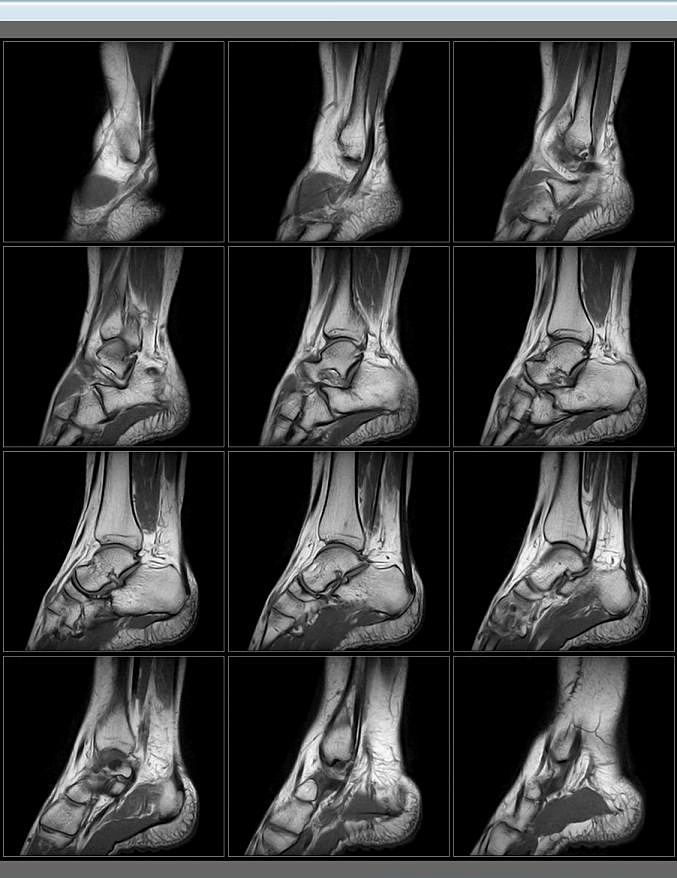

MSK imaging (imaging muscolo scheletrico)

Ortho Suite fornisce un’ampia varietà di protocolli ottimizzati per l’imaging degli arti.